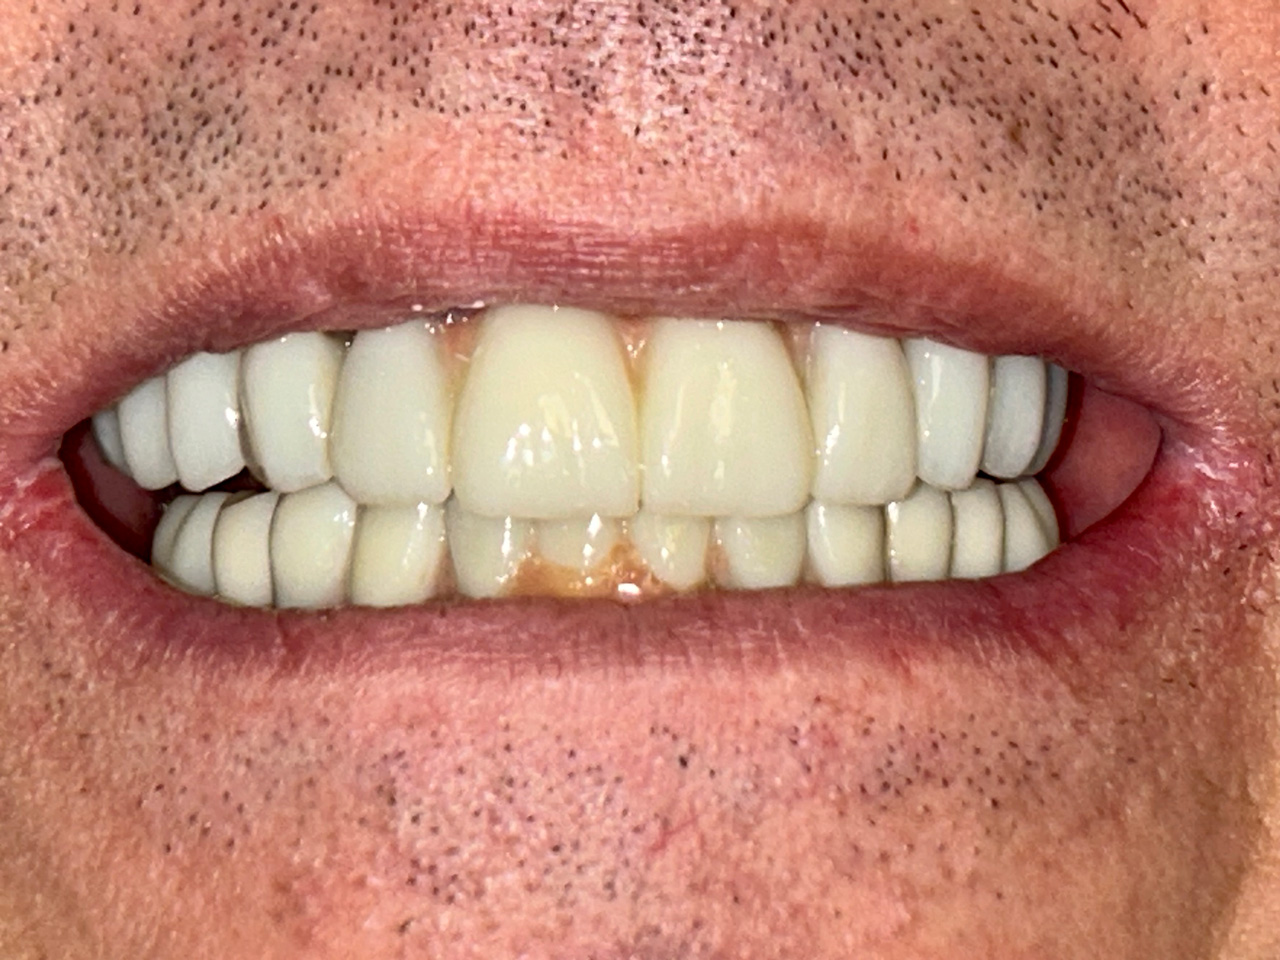

Alsó állcsont teljes rehabilitációja 72 óra alatt, azonnal terhelhető implantátumokkal súlyos paradontitisben szenvedő dohányzó páciens esetében. Az alsó állcsont fogai mind mozogtak az előrehaladott fogágypusztulás miatt.

A fogakat eltávolítottuk, a gyulladt, fertőzött csontot kitakarítottuk, kifertőtlenítettük, majd azonnal implantáltunk.

Svájci, IHDE márkájú, azonnal terhelhető implantátumokat helyzetünk be, és ezekre harmadnapra rögzített, hosszútávú, fémvázas, esztétikus műanyaggal leplezett hidat ragasztottunk be.

Ezt az ideiglenes hidat a sebek gyógyulása miatt használjuk, de tartóssága miatt véglegesként is használható. A legtöbb esetben, ahogy itt is, 6 hónap múlva porcelán hídra cseréljük, a teljes gyógyulás után.